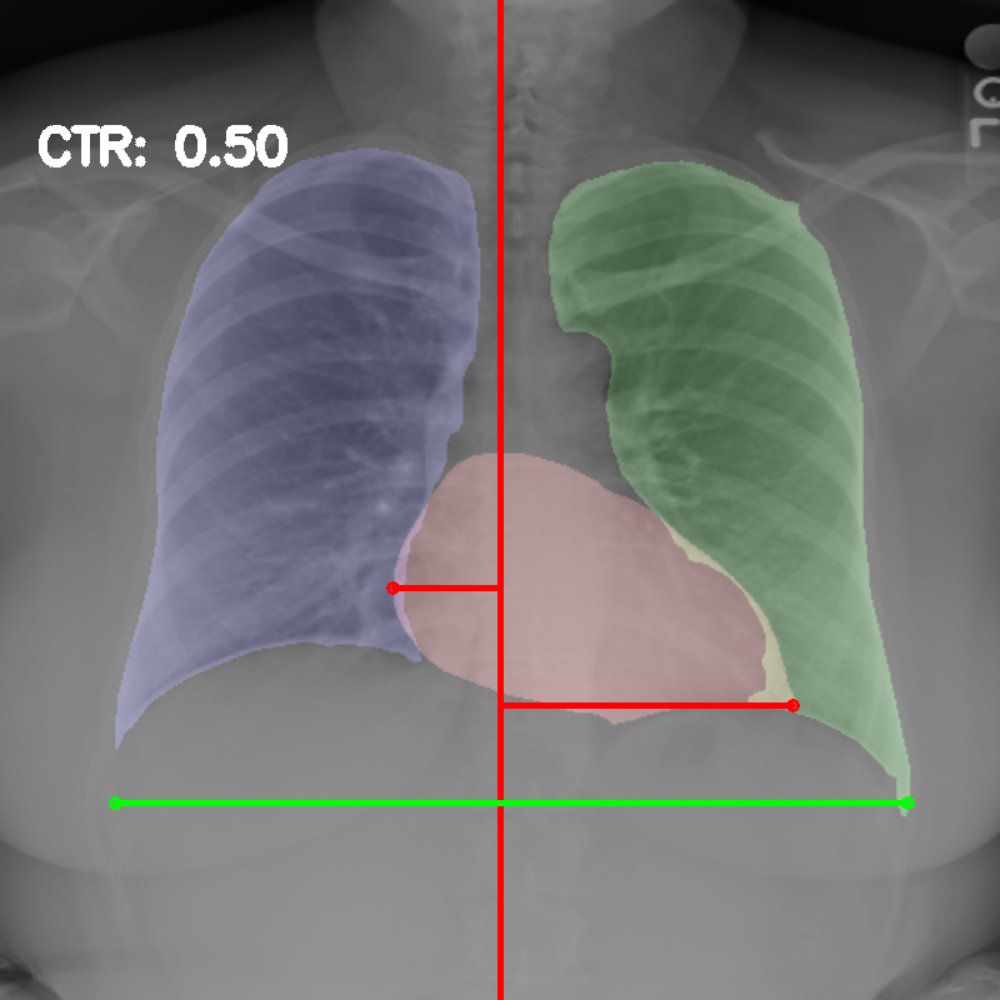

Chest radiography is the most common tool for detecting cardiomegaly due to the low cost and high availability of devices to obtain chest X-ray images. From chest X-ray images, radiologists employ CTR as one of the most important indicators of cardiomegaly due to the simplicity of the calculation. CTR of a chest X-ray image is calculated as cardiac diameter (the diameter of the heart) divided by the thoracic diameter (the diameter of the chest). Specifically, CTR can be calculated from three measurements, , the midline-to-right heart diameter, , the midline-to-left heart diameter, and , the internal diameter of chest [2, 3], as

| (1) |

where and is measured from the greatest perpendicular diameter from midline to right and left heart border, respectively. Figure 1 visualizes the details of CTR calculation. A CTR value of is generally considered to indicate the upper limit of normal.

3.5 Cardiothoracic Ratio Calculation

After obtaining the masks, we calculate CTR with equation 1. We calculate cardiac diameter, , by finding the extreme points on the x-axis of the heart mask and calculate their x-axis distance. Thoracic diameter, , is calculated from extreme points from the lung mask. Figure 4 demonstrates the calculation of each component.

After obtaining heart and lung segments, we calculated , , and and marked them on the image along with CTR value calculated from Equation 1.

Figure 6 shows examples of our CTR calculation, where CTR values along with their , and measurement points are correctly identified. In this image, cardiomegaly is correctly detected by CTR value of .

Figure 7 shows cases where our CTR calculation algorithm is incorrect due to failure to obtain accurate heart mask.